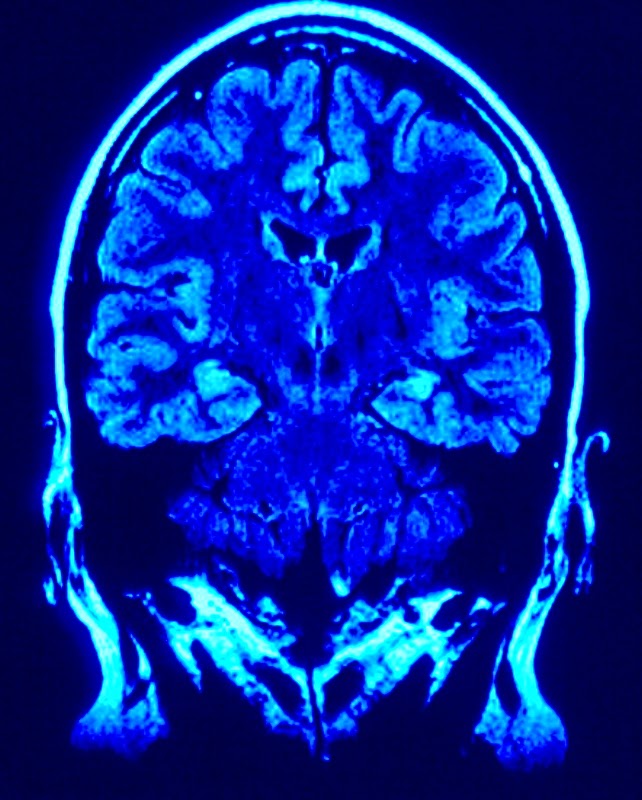

Ele afirma que as pessoas com experiência dor da fibromialgia que vem mais do cérebro e da medula espinhal do que os locais onde seus corpos se sentem a dor.

Ele acredita que a fibromialgia pode estar relacionado com a forma como o cérebro processa os sinais de dor.

"Porque vias da dor em todo o corpo são amplificados em pacientes com fibromialgia, a dor pode ocorrer em qualquer lugar, de modo que as dores de cabeça crônicas, dor visceral e sensorial hiper-responsividade são comuns em pessoas com esta condição dolorosa", disse Clauw.